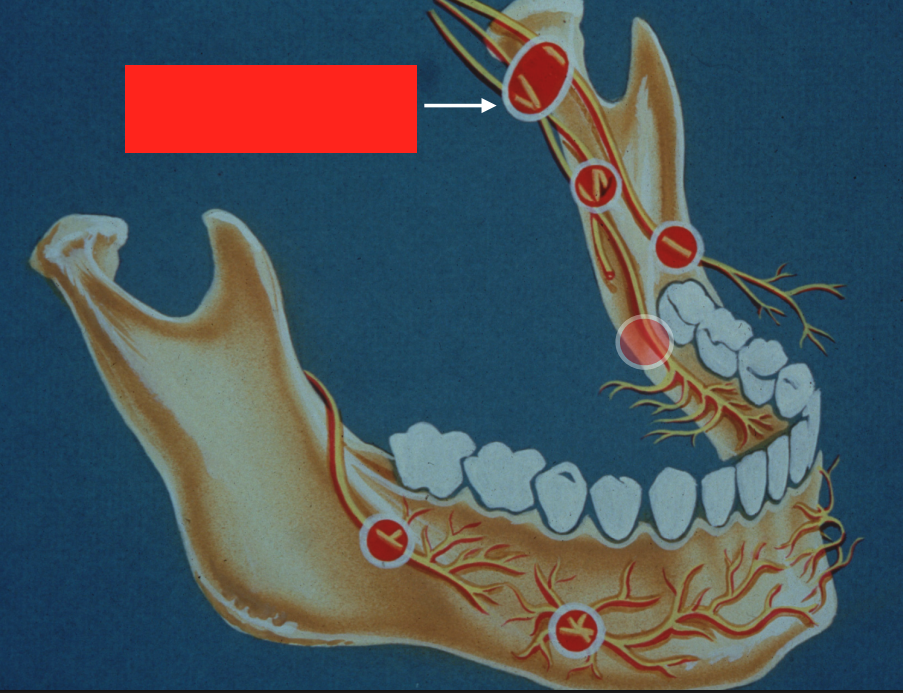

target site for which injection?

standard inferior alveolar nerve block AND lingual nerve block (can anesthetize both nerves using single injection at this site)

what nerve is indicated here?

lingual n.

lingual nerve block